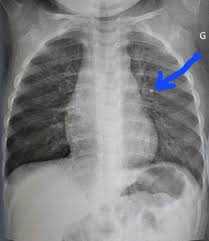

Березень в Україні традиційно присвячений подоланню туберкульозу (ТБ) — одного з найпоширеніших інфекційних захворювань у світі. Цьогоріч він проходить під гаслом: «Так! Ми можемо подолати туберкульоз. Лідерство — за державою, сила — в громадах». Воно підкреслює, що ефективна протидія ТБ Read More